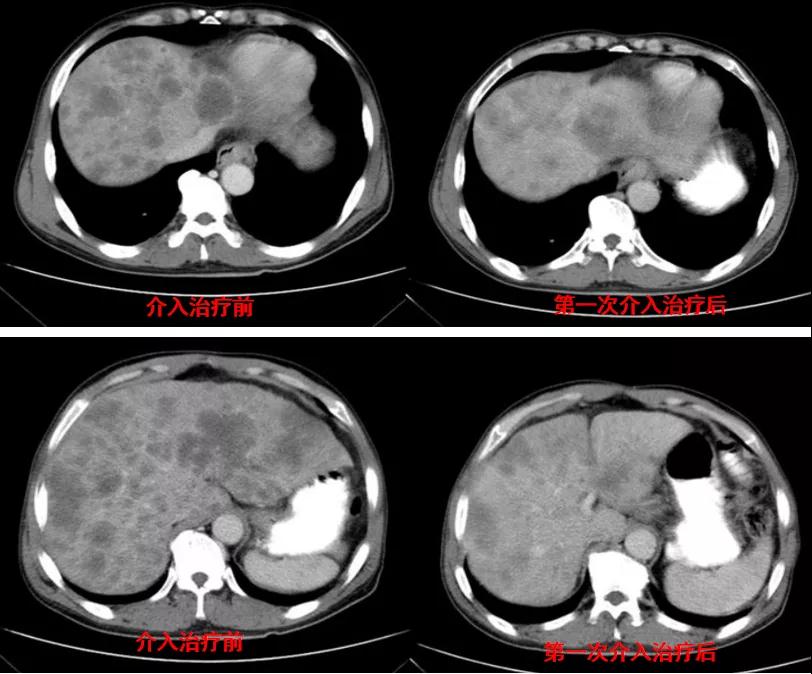

诊治经过:2020年12月16日患者行第二次经皮动脉化疗灌注栓塞术(铂类+氟尿嘧啶)治疗,并继续联合吡咯替尼治疗。结果见图3。

图3